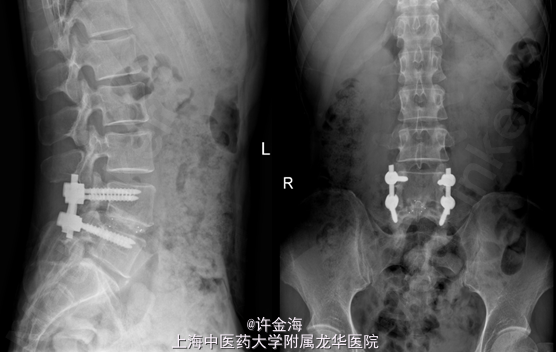

腰椎间盘突出症 术前:VAS腰6分,VAS腿8分,JOA12分 行全椎板切除减压,椎间盘摘除,cage融合,植骨内固定

术后3周访:VAS腰3分、VAS腿1分、JOA25分,JOA改善率80%